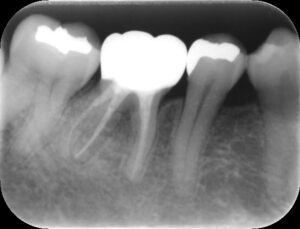

再根管治療後レントゲン。多少の違和感はあったものの、根管内部がきれいになり、排膿を認めないことから根管充填(薬を詰めること)を行った。根尖部までしっかりと薬が詰まっているのが分かる。歯根の内部がきれいな状態であれば、歯科医にはそれ以上出来ることはない。悪戯に弄り過ぎてはいけない。

同CT画像。ファイバーコアで土台を補強し、仮歯の状態で3か月の経過観察を行った。初診時にあった歯の違和感は完全に消失したため、オールセラミックで補綴処置を行うこととした。